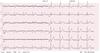

82-årig mand indbringes til skadestue/FAM. I forbindelse med en badmintonkamp er han blevet utilpas. Han er nu vågen omend lidt nervøs ved situationen. Han er ellers sund og rask. I skadestuen tages nedenstående ekg. Hvad er den mest korrekte EKG-diagnose?

- Atrieflimren med 3:1 overledning

- Atrieflimren med 4:1 overledning

- Ventrikel Takykardi (VT)

- Atrieflagren med vekslende overledning

- Atrieflagren med 1:1 overledning

82-årig mand indbringes til skadestue/FAM. I forbindelse med en badmintonkamp er han blevet utilpas. Han er nu vågen omend lidt nervøs ved situationen. Han er ellers sund og rask. I skadestuen tages nedenstående ekg. Hvad er den mest korrekte EKG-diagnose?

- Atrieflimren med 3:1 overledning

- Atrieflimren med 4:1 overledning

- Ventrikel Takykardi (VT)

- Atrieflagren med vekslende overledning

- Atrieflagren med 1:1 overledning